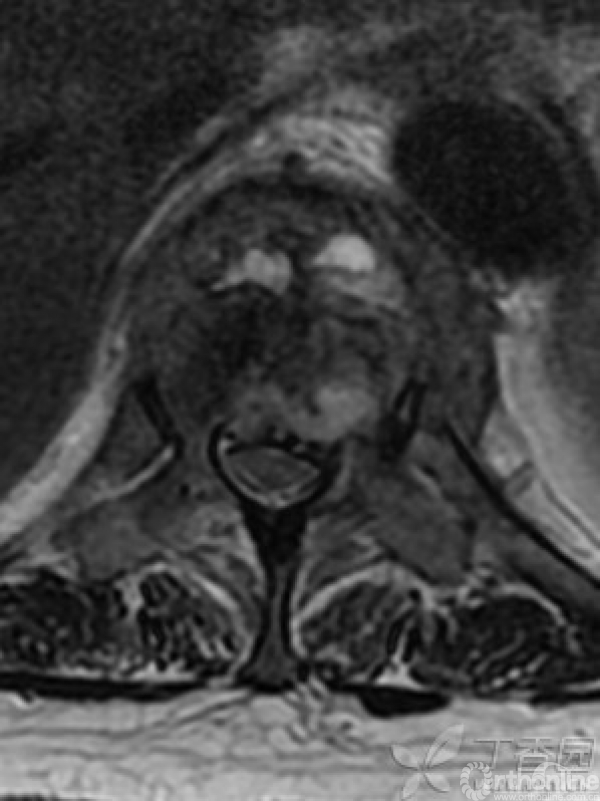

胸椎多椎体病变,如果诊断和治疗?